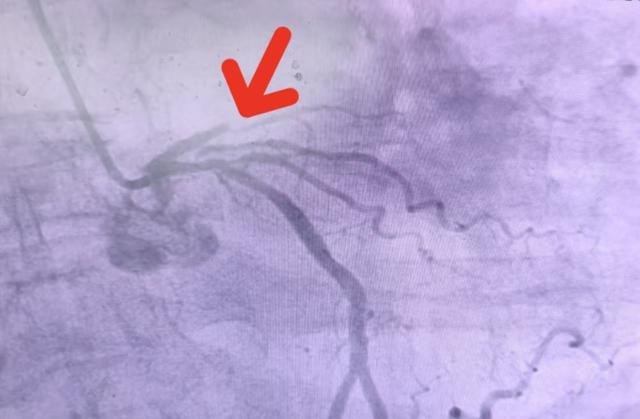

(▲冠脉造影提示前降支近端完全闭塞)

11时54分,桡动脉穿刺成功,通过手腕处针眼大小的微小创口,建立起微创生命通道;

11时58分,冠脉造影精准锁定病灶,确认患者左冠状动脉前降支近端100%闭塞;